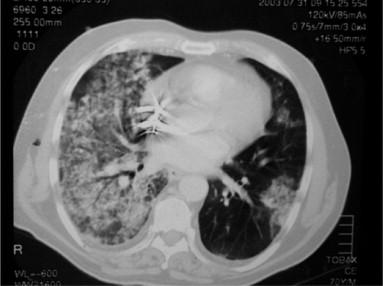

Cuando se presenta hemorragia alveolar, algunos síntomas comunes incluyen la presencia de infiltrados alveolares en la radiografía de tórax, disnea (dificultad para respirar), anemia (debido a la pérdida de sangre), hemoptisis (expectoración de sangre) y, ocasionalmente, fiebre. Estos signos y síntomas son indicativos de un proceso inflamatorio y/o daño en los pulmones que lleva al sangrado.

Un aspecto relevante para el diagnóstico de la hemorragia alveolar es la rápida resolución de los infiltrados pulmonares difusos en un período de tiempo corto, específicamente dentro de los 2 días posteriores a su aparición. Esta rápida resolución puede servir como una pista importante para diferenciar la hemorragia alveolar de otras condiciones pulmonares que podrían presentar síntomas similares pero con un curso clínico diferente.